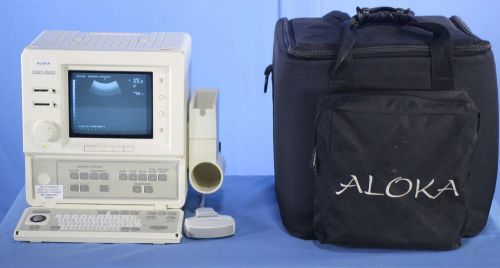

Aloka SSD-500 Portable Ultrasound System for Veterinary or Human with Warranty!